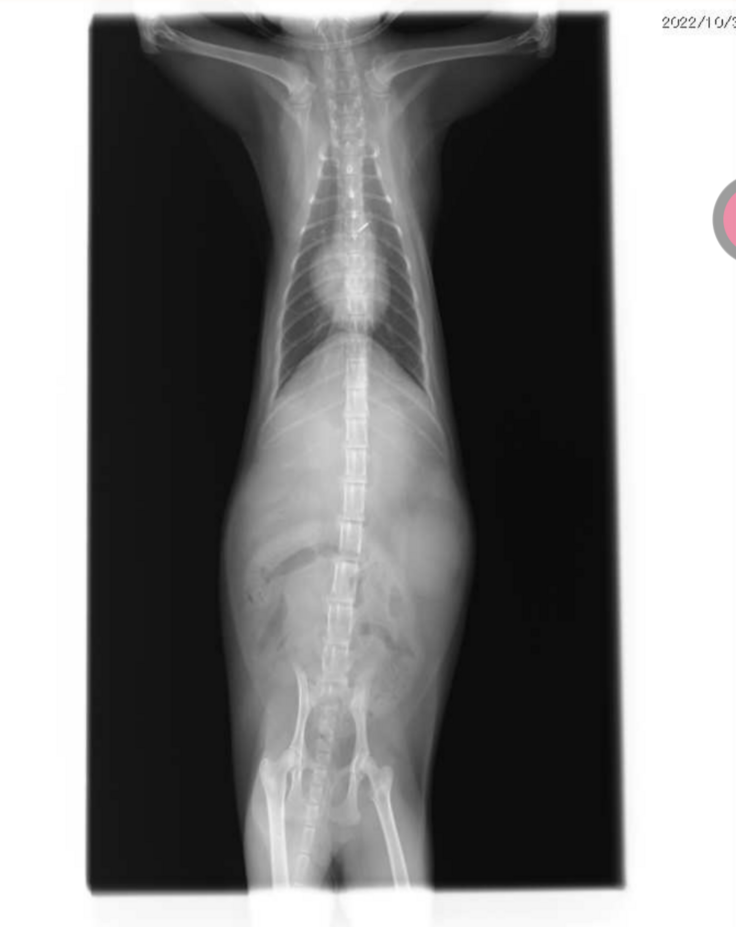

FIPという結論は以下の血液検査やエコー検査により腎臓や目などに多くの肉芽腫がみられ、やや腹水が見受けられることから、ドライタイプ中期と診断されました。

【病院から掲載の許諾を得ております】